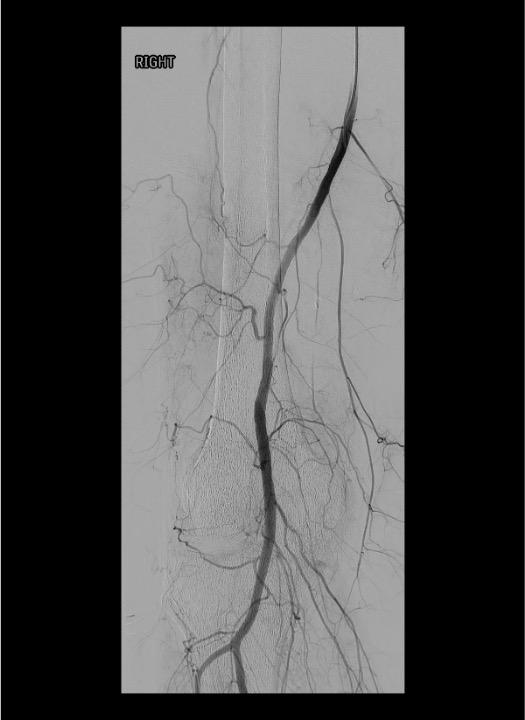

Baseline angiography: SFA and popliteal artery runs in AP and oblique projections to identify all genicular arteries and their branching patterns.

Selective catheterization: 4 Fr catheter (Cobra, Berenstein, or SOS Omni) to engage the popliteal; 2.0–2.4 Fr microcatheter coaxially advanced into each target genicular artery.

Angiographic hyperemia / synovial blush in the symptomatic territory is the primary target. This appears as a late-phase parenchymal blush beyond the normal capsular stain.

Pre-embolization selective genicular angiogram demonstrating hypertrophied vessels and synovial hypervascularity in the territory of the patient's pain.Post-embolization angiogram showing pruning of the abnormal hypervascularity with preserved flow to normal tissue — the desired endpoint.